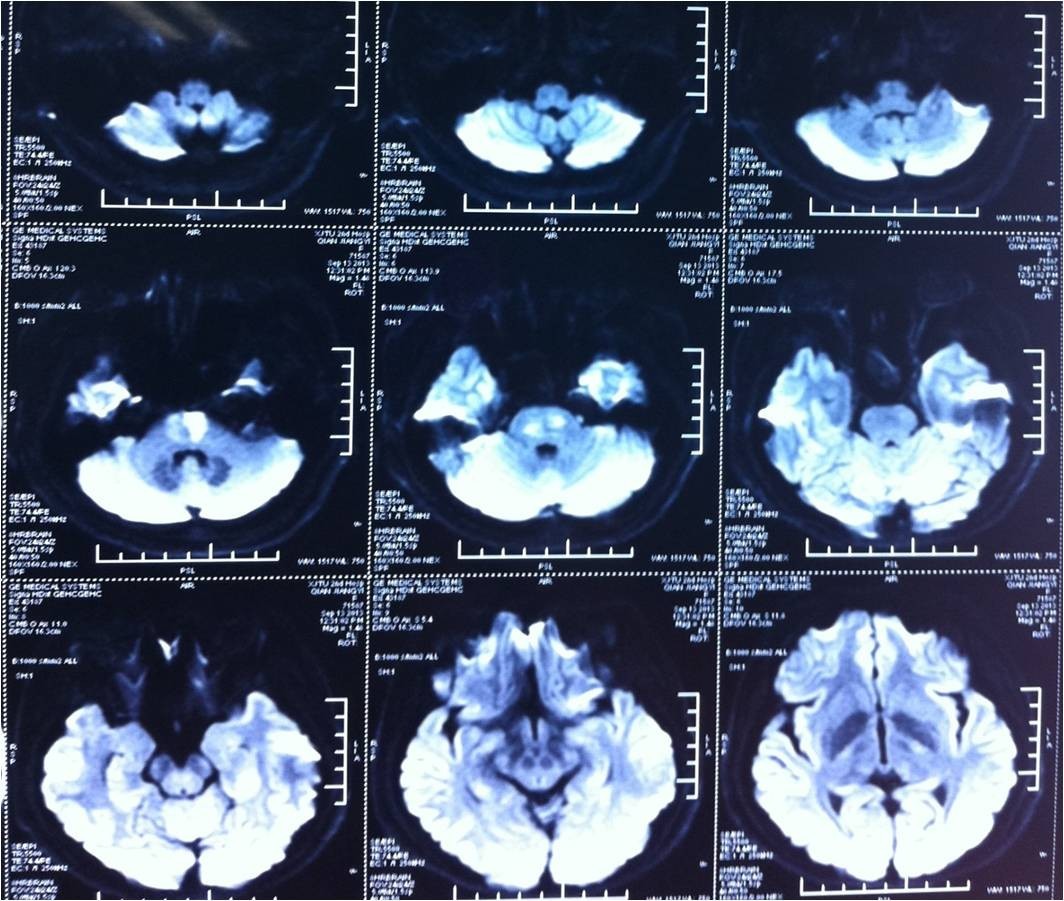

》查体:T37.4℃,BP101/60mmHg,言语不能,双侧面瘫,张口不能,吞咽障碍,左上肢肌力3级,下肢1级,右侧上下肢肌力0级,上肢肌张力减低,下肢增高,双侧病理征阳性,脑膜刺激征阴性;

》头颅CT未见异常。